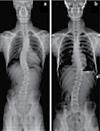

교통사고 후유증 / 목 통증 / 목 디스크 / 오십견 / 어깨통증 말초신경장애: 손, 발, 다리의 통증, 저림, 근육약화감, 감각상실 (편)두통 / 불면증 / 어지러움 / 턱관절 장애(TMJ) 척추측만증(Scoliosis) / 척추협착증 / 허리수술 후유증 허리통증 / 허리 디스크 / 관절염 / 좌골신경통 / 고관절, 발목, 손목 통증 ▪ ▪ ▪ ▪ ▪ ▪ ▪ ▪ ▪ 최첨단 목/허리 디스트 치료기기 최신형 디지털 X-ray 시설 Therapeutic Massage ▪초음파, 전기치료 Gonstead Chiropractic 교정치료 치료 진료과목 교통사고 치료 전문 자동차 보험 건강 보험 상해 보험 Southern California University of Health Science Doctor of Chiropractic 콜로라도주 척추신경 보드 정회원 캘리포니아주 척추신경과 보드 정회원 National Board 척추신경과 정회원 손석기 D.C. 원장, 척추신경 전문의 chiro1health@gmail.com Open Hours 월/수/금 9am-6pm 화/목: 2pm-6pm 청소년을 위한 척추교정 프로그램